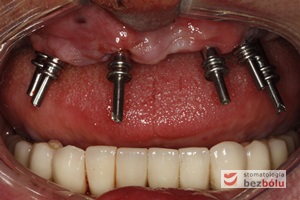

Ekspozycja implantów w szczęce - przesunięcie płata z podniebienia na stronę wargową w celu zwiększenia objętości dziąsła

Ekspozycja implantów w szczęce – przesunięcie płata z podniebienia na stronę wargową w celu zwiększenia objętości dziąsła